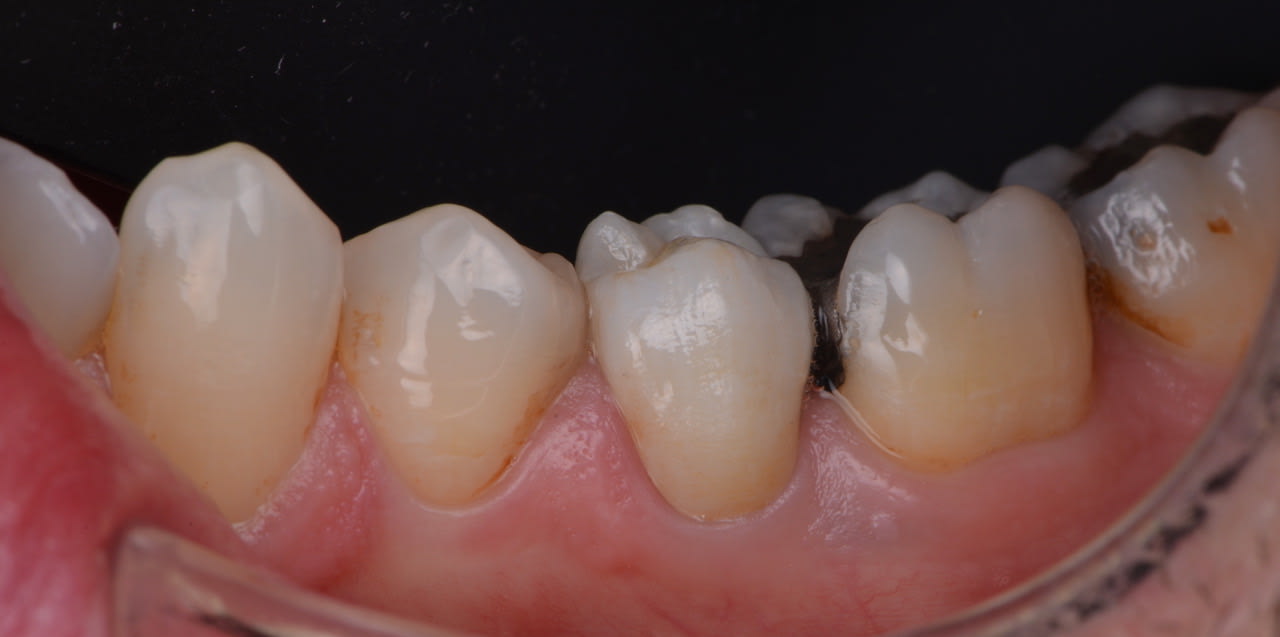

Qui d'entre vous a une full zircone en bouche ?

J'en ai une sur ma 35 depuis un an et rien à signaler.

Elle est très belle... T as une radio ?

On dirait une occlusion inverse .

Au quel cas le réglage est + facile .

La 5 est la zircone... La 3 et 4 ccm

3 CCM 4-5 zircones.

Vu le peu de place c'est mieux de solidariser.

Avec ces images, on comprend bien pourquoi le zircone est plus un métal qu'une céramique.